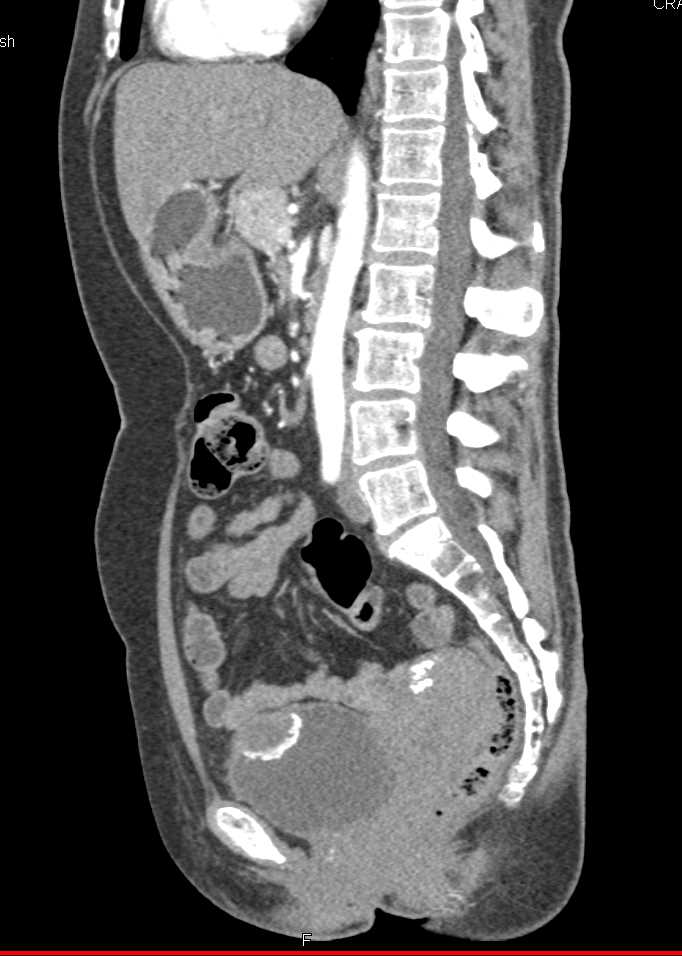

Urachal Carcinoma of the Bladder